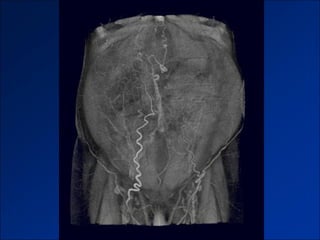

Cavernous transformation of the portal vein in a 57-year-old man with a history of recurrent

acute pancreatitis and benign portal vein thrombosis.

©2011 by Radiological Society of North America   Lee W et al. Radiographics 2011;31:905-926

Cavernous transformation ofthe portal vein in a 57-year-old man with a history of recurrent acute pancreatitis and benign portal vein thrombosis. ©2011 by Radiological Society of North America Lee W et al. Radiographics 2011;31:905-926

• #29 Cavernous transformation of the portal vein in a 57-year-old man with a history of recurrent acute pancreatitis and benign portal vein thrombosis. Axial contrast-enhanced CT image obtained during the venous phase shows multiple serpentine enhancing collateral vessels (arrows) at the hepatic hilum and an obliterated main portal vein, findings indicative of cavernous transformation of the portal vein in the setting of long-standing thrombosis.